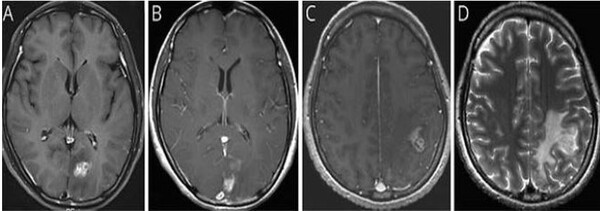

이번 연구는 서울대병원에 내원한 40대 여성 환자를 대상으로 이루어졌다. 환자는 심한 두통과 구토 증세로 병원을 방문했으며, 초기 뇌 MRI에서 좌측 후두엽에 불규칙하게 조영된 종양성 병변이 발견되어 뇌종양이 의심됐다. 의료진은 수술을 권유했지만, 환자는 증상이 일시적으로 호전되자 치료를 거부하고 퇴원했다.

환자는 7개월 후 다시 극심한 두통과 전신 발작으로 병원을 방문했다. 후속 MRI에서 병변이 좌측 후두엽에서 좌측 두정엽으로 이동한 것이 확인됐고, 이 병변 이동은 스파르가눔증의 대표적인 진단 단서가 됐다. 환자는 과거 오염된 연못물을 마시고, 날생선 및 익히지 않은 야생 동물 고기를 섭취한 이력이 있어 의료진은 기생충 감염을 염두에 두고 ELISA 검사와 정위적 생검을 시행했다.

검사 결과, ELISA 검사와 뇌척수액(CSF) 검사에서 스파르가눔증 항체가 검출됐으며, 정위적 생검에서는 염증성 육아종이 확인됐다. 이후 개두술을 통해 살아있는 스파르가눔증 유충을 성공적으로 제거했다. 수술 과정에서 기생충이 살아 움직이는 모습은 영상으로 기록됐다.